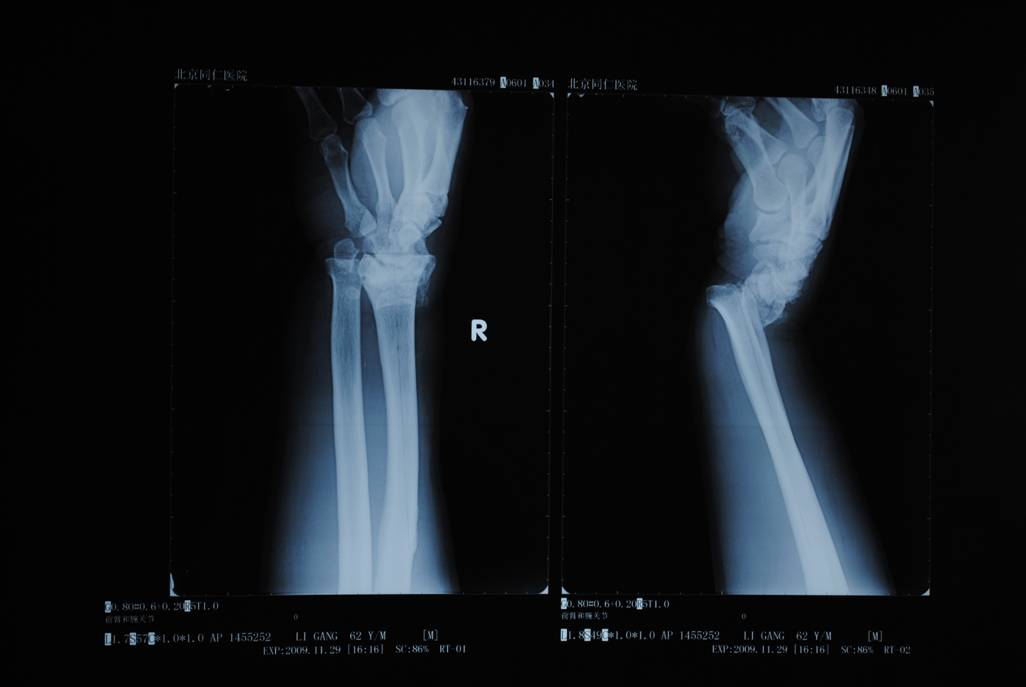

橈骨遠端骨折術前

橈骨遠端骨折術后

橈骨遠端骨折術前 橈骨遠端骨折術后

五研獨家產品組合式腕關節(jié)骨外定架,具有專利保護

組裝簡便,穿針便捷,適合各種橈骨遠端骨折及腕部矯形。斷端無X線遮擋。